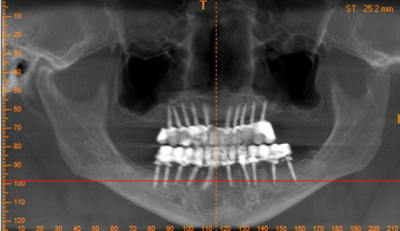

> Hi hi plus de 14 implants....

si j'ai bien compté....y en a 40...là c'est sûr çà doit tenir....ah oui...il aurais pu encore rajouter des clavettes en travers ou des contres écrous....;-))

c'est pas un implanto mexicain par hasard?

je ne me rappelle plus de son nom mais ce dont je me souviens c'est qu'un exclusif mexicain, fervent religieux, pose toujours autant d'implants que de racines naturelles car "si Dieu a conçu la nature comme cela il faut la reconstruire de la même façon".

maintenant, il semble oublier que les dents naturelles sont nettoyables contrairement à ses reconstructions. Je me demande s'il n'a pas plus la foi en le pognon qu'en Dieu:))